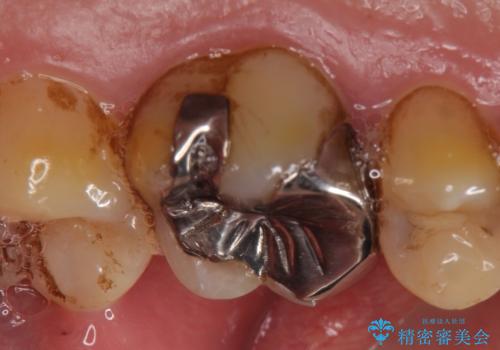

- 他院にて左上6番目の歯の神経が死んでいるといわれたので診て欲しいといらっしゃった方の症例です。

診査の結果左上6は失活していたため、根管治療を行った後にオールセラミッククラウンによる補綴を行いました。